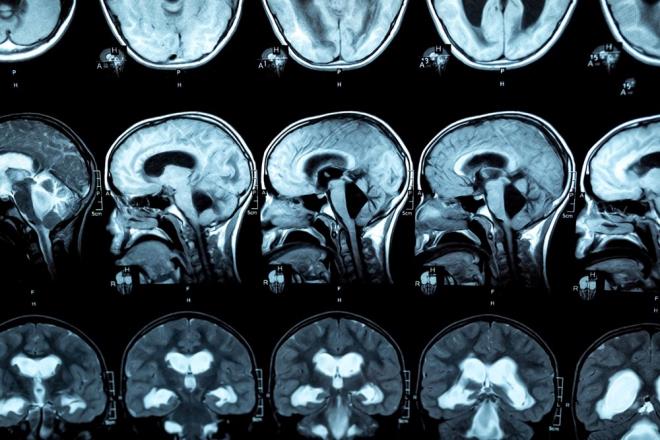

Beynimizin yalnızca yüzde 10'unu kullandığımız efsanesi bilim insanları tarafından kesin bir dille çürütüldü, ancak beyin hakkında hâlâ bilmediğimiz çok şey var. Bilim insanlarının onlarca yıldır kafasını karıştıran bir vaka da bunların başında geliyor.

Yıllar önce kimliği bilinmeyen Fransız bir adamın beyninin yüzde 90'ının eksik olduğu ancak normal bir yaşam sürdüğü tespit edildi. Bu durum, beyin ve insan bilinci hakkında var olan bilgileri yeniden sorgulamaya yol açtı.